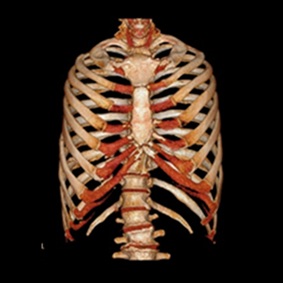

また、撮影した画像を重ね合わせることにより立体画像を構築し、より細かい診断ができます。

フィリップス社製のingenuity core(64列)というマルチスライスCT装置を導入しています。

この装置は1回転の間に64画像(スライス)を撮影することが出来るため、短時間で広範囲の撮影を行うことができます。

また、心臓のような動きのある臓器でも高精細な画像を得ることができます。